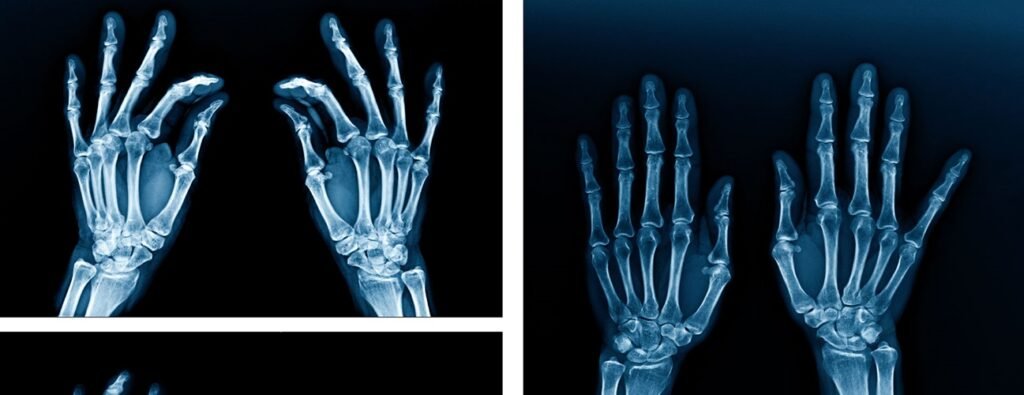

എക്‌സ്-റേയിൽ വ്യക്തത: ചികിത്സയ്ക്ക് കൂടുതൽ സുരക്ഷ

ഈ ജൈവ സിമന്റിന്റെ പ്രധാന സവിശേഷത റേഡിയോപേക്ക് സ്വഭാവമാണ്. അതായത്, എക്‌സ്-റേയിൽ ഇത് വ്യക്തമായി ദൃശ്യമാകും.

കുറഞ്ഞ തീവ്രതയുള്ള എക്‌സ്-റേ ഉപയോഗിച്ച് തന്നെ ചികിത്സാ പുരോഗതി വിലയിരുത്താൻ കഴിയുന്നതാണ് ഇതിന്റെ വലിയ ഗുണം. ഇതുവഴി രോഗികൾക്ക് കൂടുതൽ സുരക്ഷയും കൃത്യതയുള്ള ചികിത്സയും ഉറപ്പാക്കാം.